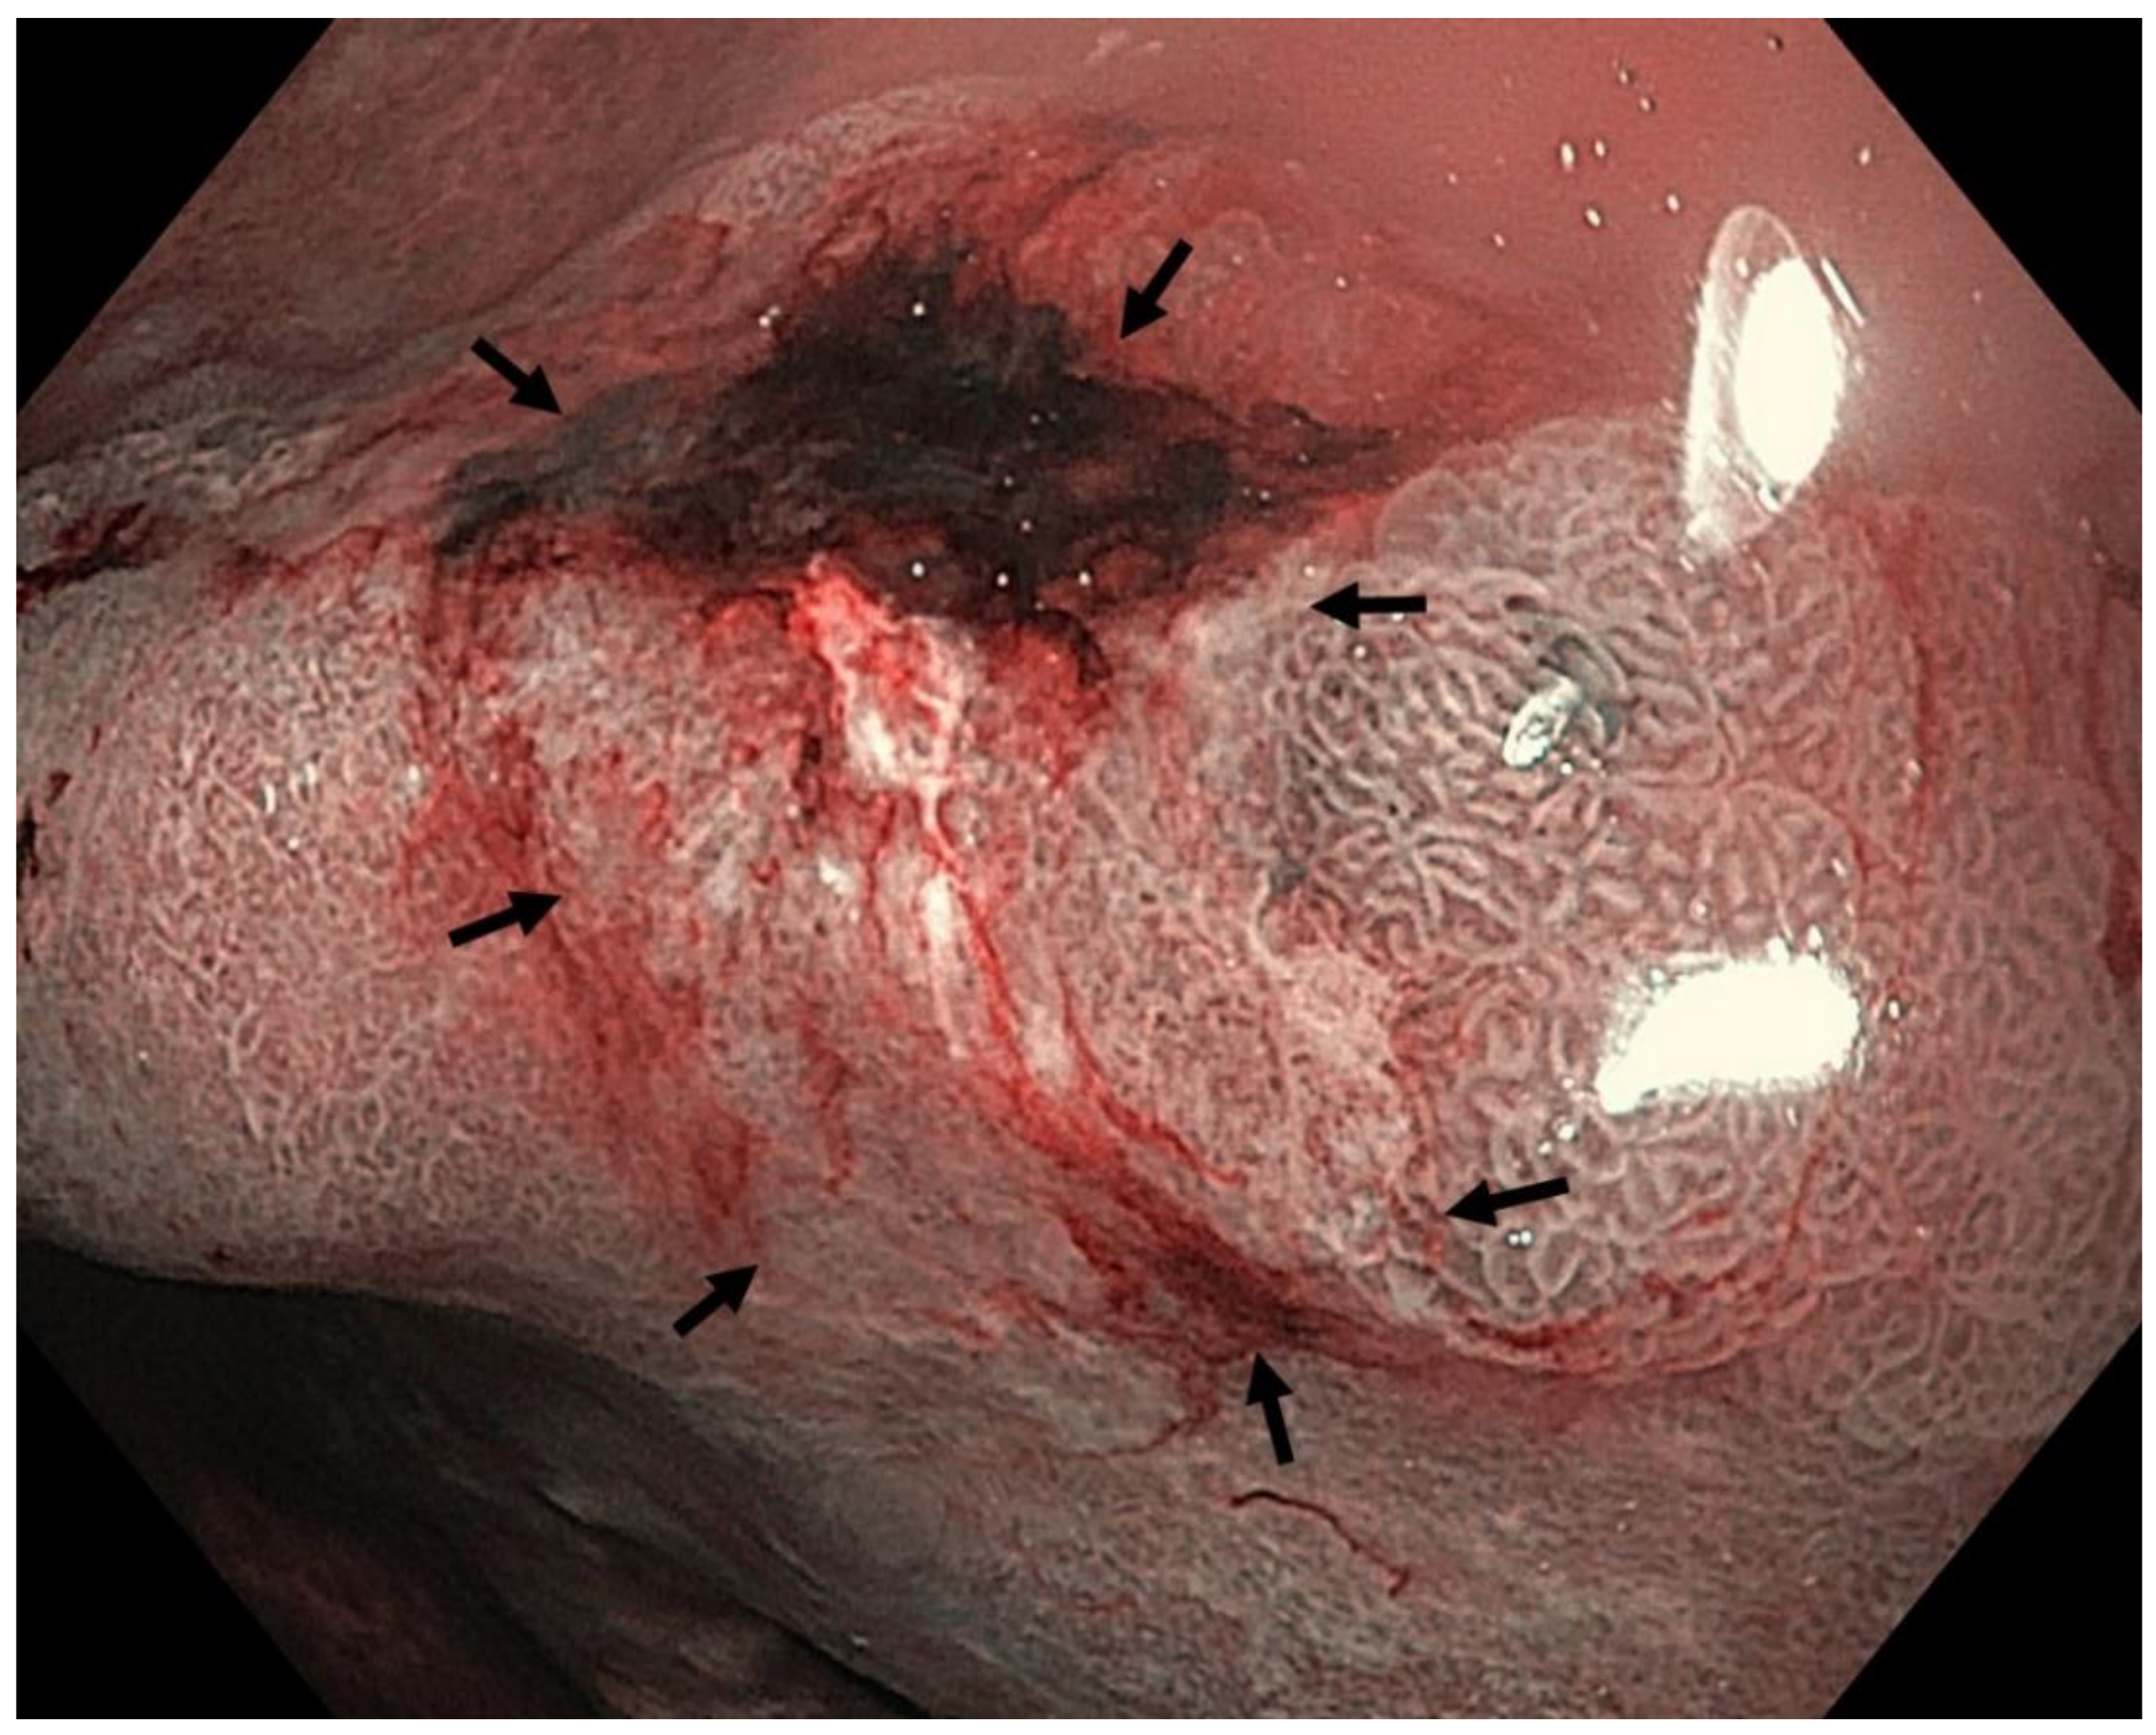

Four features indicative of gastric corporal atrophy have been reported: pallor, loss of gastric folds, prominence of vessels and atrophic border [113,147], Figure 3 and Figure 4.

Grey-white mildly elevated plaques which are surrounded by patchy pink and pale areas are the typical appearance of intestinal metaplasia, Figure 5 and Figure 6. Standard endoscopy alone is not reliable for the diagnosis of intestinal metaplasia. Using image-enhanced and magnification endoscopy, intestinal metaplasia can be recognized in the gastric body by a “groove-type pattern”, which is similar to that observed in the antrum due to the oblique structure of the glands, and is easy to differentiate from the normal straight glands. Intestinal metaplasia in the antrum however is difficult to characterise, as the pre-existing oblique glands are not dissimilar to the “grooved” glands of intestinalisation. The “light blue crest” and “marginal turbid band” (see below) are helpful features to distinguish gastric intestinal metaplasia from the normal antral mucosa, Figure 7 [113].

The marginal turbid band is defined as an enclosing, white turbid band on the epithelial surface/gyri, and the light blue crest is defined as a fine, blue–white line on the crest of the epithelial surface/gyri [148].